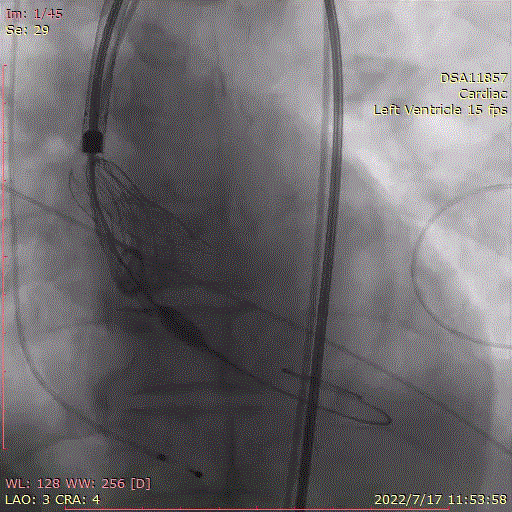

回收后,重新调整到工作位后,造影显示瓣膜位置良好,第2次0位释放,释放脱钩后瓣膜形态、位置良好,冠脉血流灌注正常,微少量瓣周漏,术后跨瓣压差降至0mmHg。

回收,调整位置

第二次0位释放

瓣膜有序脱钩

角度造影